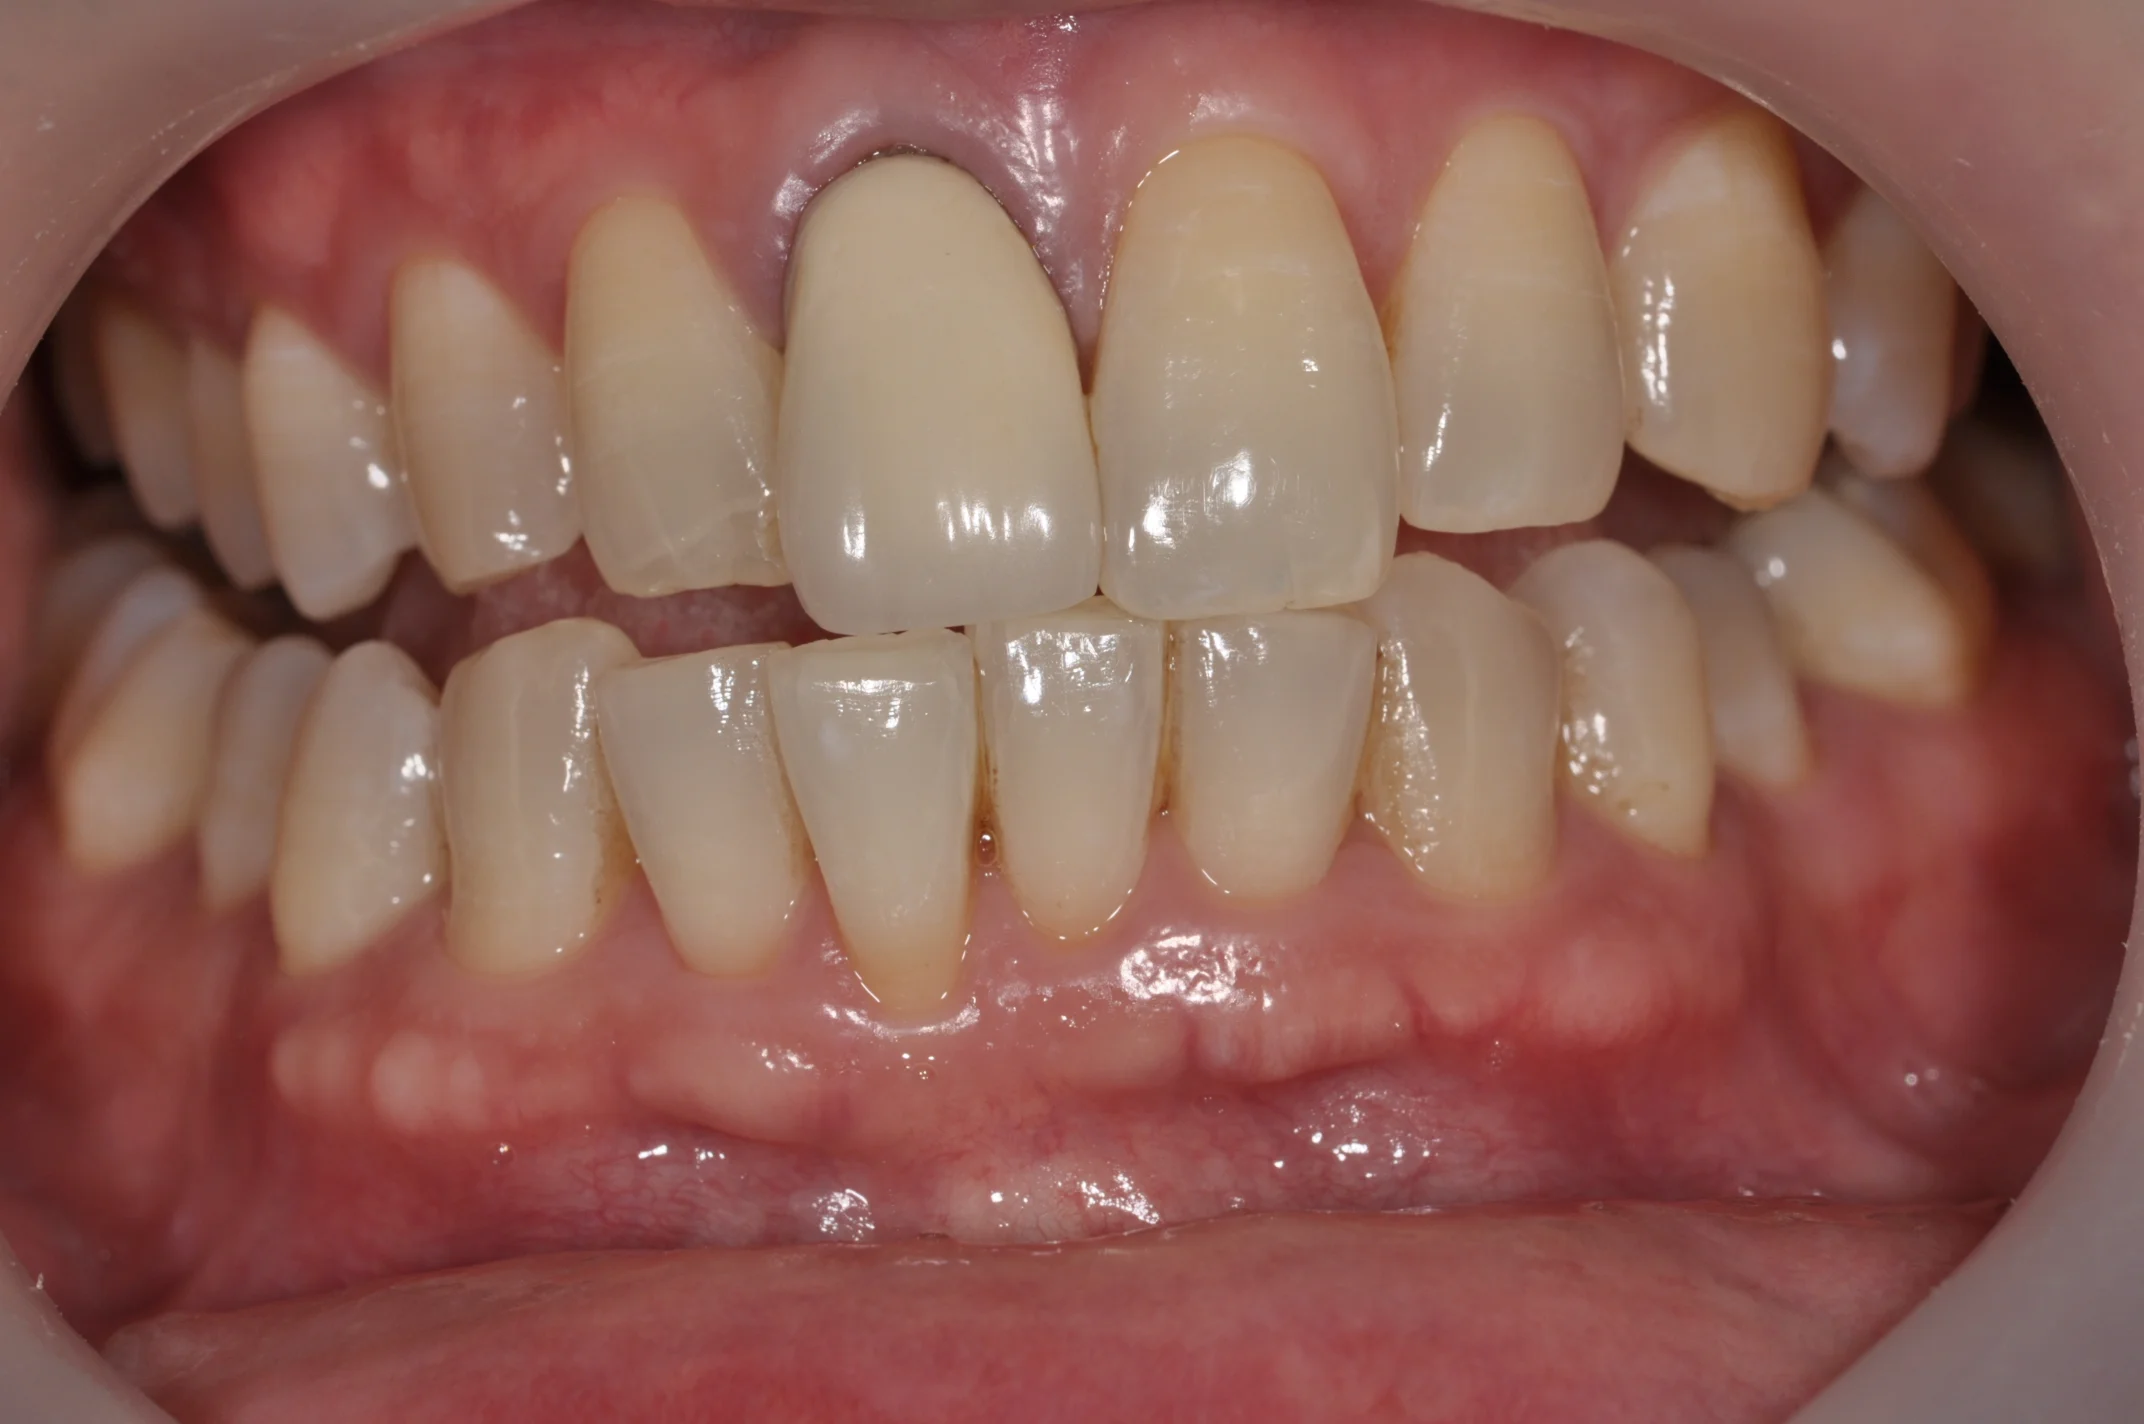

Failing Natural Central Incisor

(Upper front tooth)

Jason Ho Issue implant-crown.jpg

Replacement with a dental implant and full ceramic crown